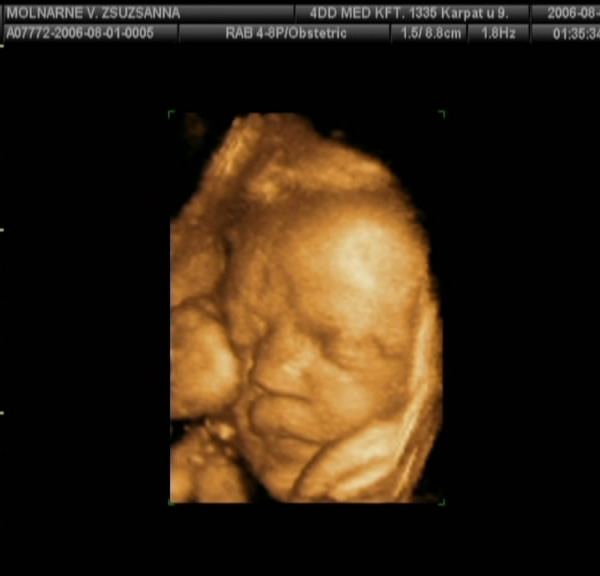

Voltunk kedden 4d-s uh,össze-vissza adatokat mért a gép.

2023g baba súlya, ami 31 hetesnek,

feje 30hétnek , combcsontja 31,pocak 35,végül kidobta,hogy 32 hetesnek felel meg a méretei alapján baba.

3 kilonál ne számítsak nagyobb babára azt mondta a dokinéni,de az én méreteimhez ez is bőven elég lesz.